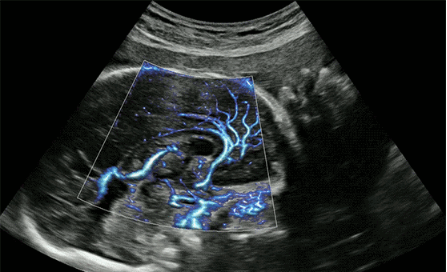

CrystalLive?是三星最新的超聲成像引擎,同時增強了2D圖像處理能力、3D渲染能力和彩色信號處理能力,能夠在復雜情況下提供出色的圖像性能,具備檢測外周血管、微循環(huán)血流的能力。